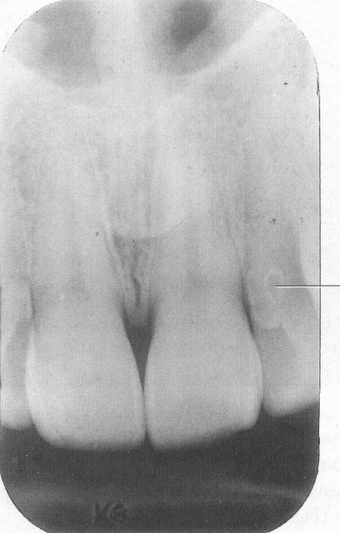

Mesiodens

Mesiodens between centrals